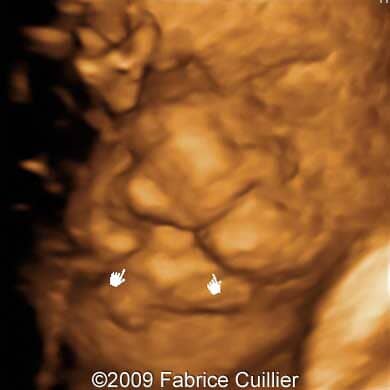

The following images show a case of an unilateral cleft lip diagnosed at 25 weeks old fetus of a 22-year-old mother with non-contributive history. No other anomaly was found. Karyotyping revealed normal karyotype (46,XX) and the course of the pregnancy was uneventful. The neonate was delivered at 38 weeks and its surgery is scheduled at six months.

Images 3, 4, 5: 3D images showing unilateral cleft lip.